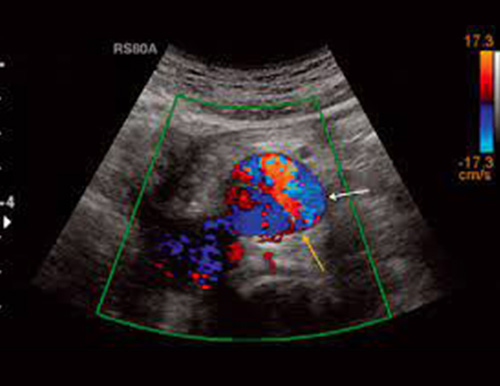

Color Doppler

This type of Doppler uses a computer to change sound waves into different colors. These colors show the speed and direction of blood flow in real time. Power Doppler, a newer type of color Doppler. It can provide more detail of blood flow than standard color Doppler.